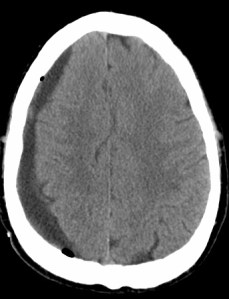

In the case of non-penetrating head trauma, the one immediate concern is to make sure that there is no intracranial bleed. Intracranial bleeds can be tricky, producing symptoms at one moment and not at later periods. This is what happened to Natasha Richardson who hit her head while skiiing. She felt badly and then interpreted a subsequent lucid interval as a sign that all was well. All was not well and by the time this was realized, Ms Richardson was out of time. If there is any possibility of an intracranial bleed, going to an ER to check that out is the right thing to do. Here is what you hope you don’t find:

This is an image of a bleed provided by a reader. The owner of this brain fell off his bike and hit his head. He only developed symptoms 3 months later. He went to the hospital and this slowly developing bleed was revealed. He was lucky and he is fine today.

Hi Peggy, I sent your blog to my brother (owner of the brain shown above) and his doctor friend Steve who made this observation – “Hi Kit. If you look carefully at your scans in addition to the SDH you will also see an advanced case of chronic bilateral biventricular interstitial stubbornness!!”